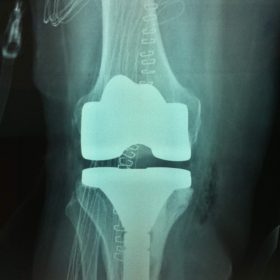

Σε αυτό το σημείο η Αρθροπλαστική Γονάτου αποτελεί μονόδρομο.